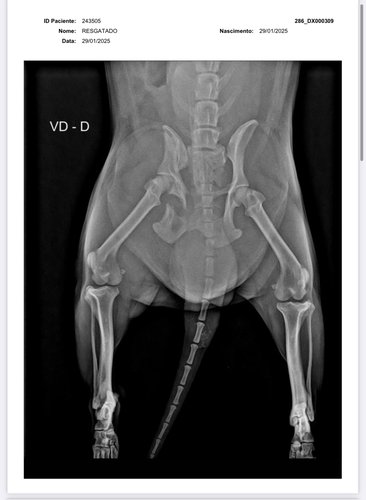

olá, eu sou a Samira, ajudo em uma ong de animais em Vilhena-RO e também resgato animais por conta própria. Encontrei esse pequeno cachorrinho abandonado a dias na chuva, sentindo tanta dor a ponto de não aceitar um sachê de comida. Levei ao veterinário e após buscar vários orçamentos, cheguei ao valor da vakinha, juntamente com a clínica Veterinária SOS animal, para a cirurgia do pequeno guerreiro. Não possuo condições de arcar com 100% da cirurgia, portanto, peço encarecidamente a ajuda de vocês para me ajudar e salvar a vida desse pequeno guerreiro. * Deixo abaixo o orçamento e os exames !